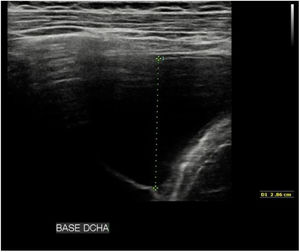

Varón de 10 años que acude por fiebre y tos de una semana de evolución, sin hallazgos en la exploración física se realiza PCR de COVID-19, que es negativa, y se envía a domicilio. A los 12 días reconsulta y en la exploración presenta hipoventilación en hemitórax derecho. En la analítica sanguínea destaca una PCR 123 mg/L; LDH 327 U/L; coagulación con: TP 58% y dímero D 5.825 ng/mL. Test rápido (ICT) con resultado positivo y PCR negativa. En la radiografía de tórax (fig. 1), se observa opacidad extensa en el hemitórax derecho con derrame pleural ocupando aproximadamente el 50% del mismo. En la ecografía torácica se comprueba derrame pleural de 7,5 cm de grosor en base pulmonar (fig. 2). Ante sospecha de COVID-19 grave, se inicia antibioterapia i.v., dosis de vitamina K y heparinas de bajo peso molecular (HBPM). A las 48 h presenta necesidad de oxígeno y empeoramiento del derrame. Se coloca drenaje pleural. El análisis bioquímico del líquido pleural presentaba leucocitos 588/uL con 93% de linfocitosis, ADA 200, proteínas 5,7 g/dL, LDH 718. Se establece diagnóstico de presunción de tuberculosis. Se realizan pruebas Mantoux (25 mm a las 72 h) (fig. 3) y QuantiFERON, que son positivas. Recibe tratamiento antituberculoso con isoniazida, rifampicina, pirazinamida y etambutol durante dos meses, seguido de cuatro meses con isoniazida y rifampicina. La evolución del paciente es favorable, se solicita test serológico ELISA, encontrándose IgG e IgM negativas.

Estudios de imagen. Ecografía torácica: Derrame pleural de hasta 7,5 cm de grosor en la base pulmonar derecha (desde línea media axilar), y de hasta 4 cm de grosor en campo medio derecho. El derrame es predominantemente anecoico, con algunos finos tabiques hiperecogénicos. Se observa alguna zona compatible con parénquima pulmonar condensado/atelectásico en profundidad al derrame.